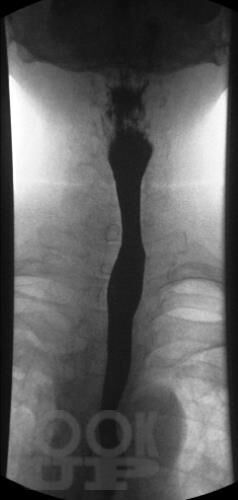

Учебное пособие разработано в соответствии с требованиями ФГОС ВО в рамках рабочей программы модуля «Госпитальная хирургия» дисциплины «Госпитальная хирургия, детская хирургия» и дисциплины «Неотложные состояния в хирургии» для обучающихся по специальности 31.05.01 «Лечебное дело». В пособии представлены наглядные изображения различной патологии органов грудной клетки и брюшной полости. Отражены методы лучевой диагностики: рентгенография, рентгеноскопия с контрастированием, компьютерная томография, эндоскопическая ретроградная холангиопанкреатография. В учебном пособии использованы оригинальные снимки, предоставленные коллективом авторов.